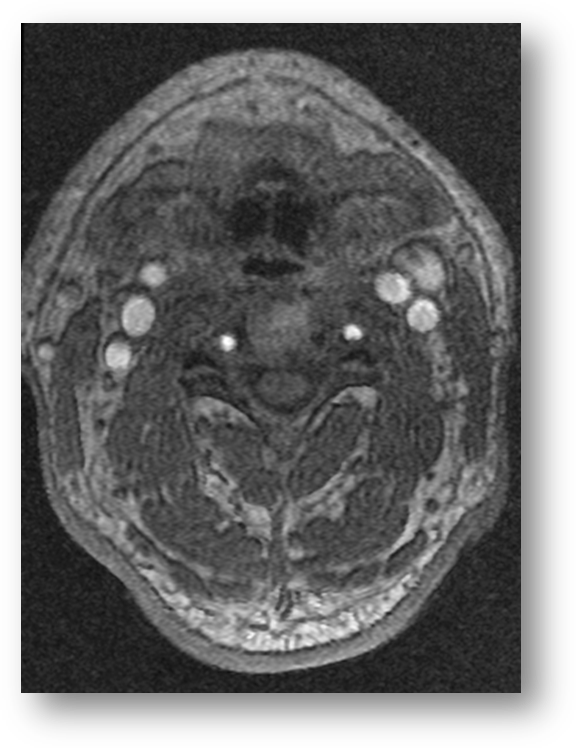

Refer to caption

Figure 4: ADC map showing hypointensity in the left periventricular MCA distributions, consistent with acute ischemic stroke. Note the marked hyperintensity of the vitreous and cerebrospinal fluid. Both are fluid-filled cavities and have a much higher diffusion coefficient than tissue.

The diffusion-weighted MRI (DWI) modality exploits the Brownian motion of water molecules within a sample, and the relative phase shift in moving water versus stationary water. The Apparent Diffusion Coefficient (ADC) is a parameter which can be mapped to provide diagnostic information. In acute ischemic stroke, cytotoxic cellular injury results in axonal edema and a subsequent decrease in Brownian motion. This is manifested as a hyperintensity on DWI and a hypointensity on the corresponding ADC map. Figure (6) is a DWI showing hyperintensity in the left MCA and PCA distributions, consistent with acute ischemic stroke. Figure (4) is an ADC map showing hypointensity in the left MCA distribution, consistent with acute ischemic stroke. Figure (5) shows an ADC map with a left parieto-occipital hypointensity reflecting left posterior circulation acute ischemic stroke. In the subacute setting, the ADC may normalize and even increase due likely to ischemia-associated remodeling and loss of structural integrity. The differential for hyperintensity on DWI includes hemorrhagic stroke, traumatic brain injury, multiple sclerosis, and brain abscesses  [62, 11, 95, 24]. DWI has long been shown in animal models to be more efficacious than T2subscript𝑇2T_{2}-weighted imaging for the early detection of transient cerebral ischemia [73, 77, 28]. Additionally, DWI has been shown to be highly efficacious in the early detection of acute subcortical infarctions [100]. DWI in conjunction with echo-planar imaging has been shown to effectively discriminate between high grade (high cellularity) and low grade (low cellularity) gliomas [104]. Of note, in spite of the relatively high specificity and sensitivity of DWI in the early detection of acute ischemic stroke, there is a small subset of stroke patients who evade DWI detection in spite of clinically evident stroke-like neurological deficits [2]. DWI tractography or diffusion tensor imaging is a form of principal component analysis in which the dominant eigendirection is used to determine the path of an axonal tract in a given voxel. This method has shown potential for further elucidation of neuronal pathways in the brain.